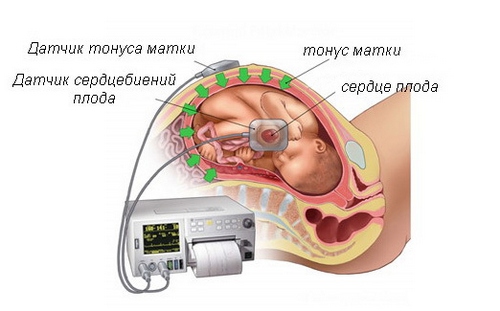

При третьому скринінгу може знадобитися кардиотокография - метод одночасної реєстрації серцебиття плода і маткових скорочень

Кардіотокографія - метод оцінки стану дитини на підставі наступних показників:

На КТГ жінка перебуває в лежачому або напівлежачому положенні на спині. До живота прикріплюється кілька датчиків: ультразвуковий для реєстрації серцебиття дитини і тензодатчик для фіксації скорочень матки. Процедура триває від півгодини до години.